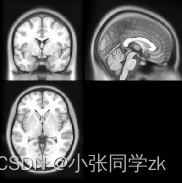

图2.8.27 脑核磁图像和脑掩膜图像 [19]

对ICBM152(脑成像国际联盟(International Consortium for Brain Mapping)所提供的标准空间模板)进行颅骨剥离的结果如图2.8.28所示:

图2.8.28 颅骨剥离